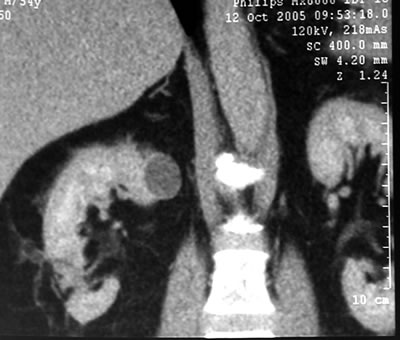

Спиральная

компьютерая томография (СКТ)

в нижнем сегменте правой почки

образование размером 30х33х36 мм, не накапливающее

контрастное вещество (max 15 HU).

|